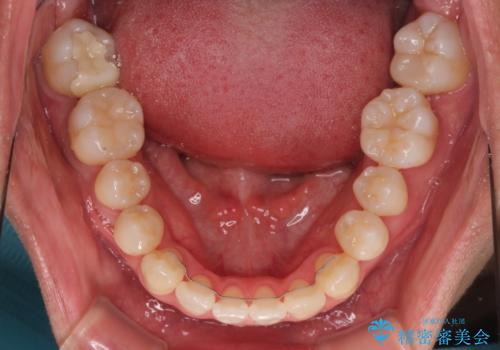

歯列弓の拡大により約1年で矯正治療を終えることができました。

正中も合わせることができ、非常にきれいに仕上がりました。